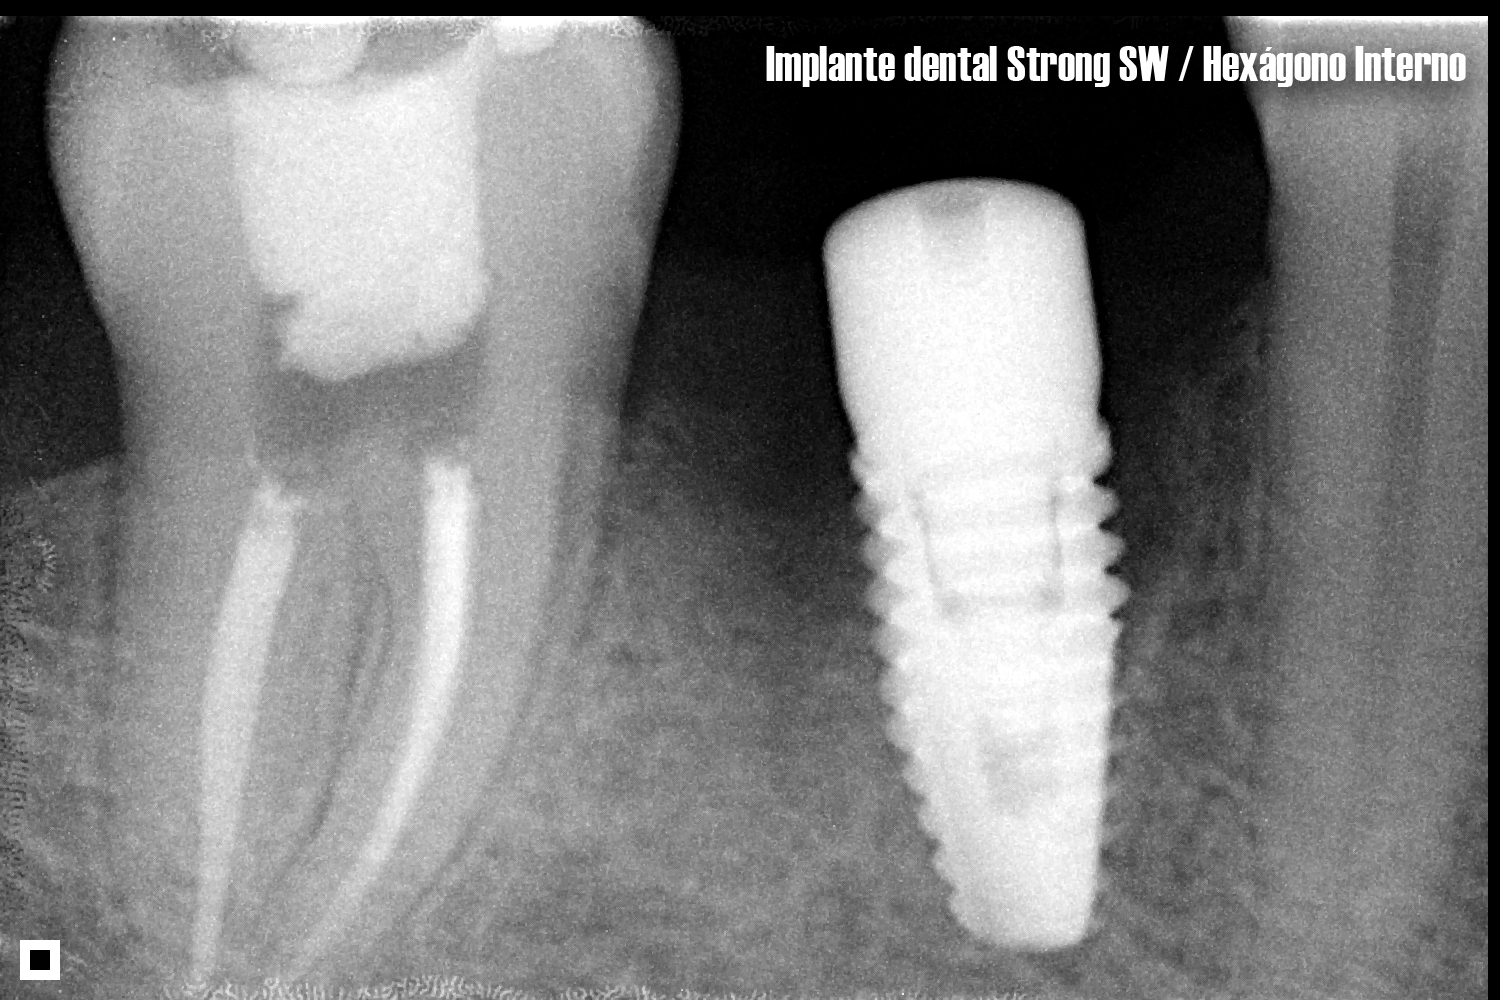

HEXÁGONO INTERNO

- Fabricado en Titanio Comercialmente Puro (Ticp)

- Estéril por radiación Gamma

- Superficie tratada con doble acondicionamiento ácido hasta la plataforma del implante

Conexión interna:

- Mayor resistencia mecánica

- Sin transportador

- Alta resistencia a las fuerzas masticatorias

- Perfil de roscas más cortantes que facilitan la instalación del implante

- Micro-roscas cervicales que aumentan el área de contacto óseo y mejoran la disipación de las fuerzas oclusales

- Alta estabilidad primaria con traba apical y cervical

- Mejor sellamiento biológico

- Macro-geometría híbrida, cuerpo cilíndrico y ápice cónico

- Permite el uso de la TécnicaPlatform Switching

- Tres opciones de llaves para su instalación:

- Llave de contra-ángulo (CMHI01 o CMHI02)

- Llave de ratch (CCIH 20 o CCIH 24)

- Llave digital (CMH 20 o CMH 24)

- Posee rosca externa con diámetro de cuerpo de 3.8mm

- Posee rosca interna con diámetro de 1.8mm

- Plataforma con diámetro de 3.8mm

INDICACIONES

Indicado para la rehabilitación con carga inmediata, precoz o tardía

- Para espacios mesio-distales pequeños: incisivos centrales superiores, caninos y premolares y también para molares.

- Implantes unitarios o múltiples

- Posibilita la instalación en cualquier tipo de hueso, inclusive posterior a exodoncias

DIÁMETROS HEXÁGONO INTERNO

3.80, 4.50, 5.00mm

LONGITUDES HEXÁGONO INTERNO

8.50, 10.0, 11.5, 13.0, 15.0mm